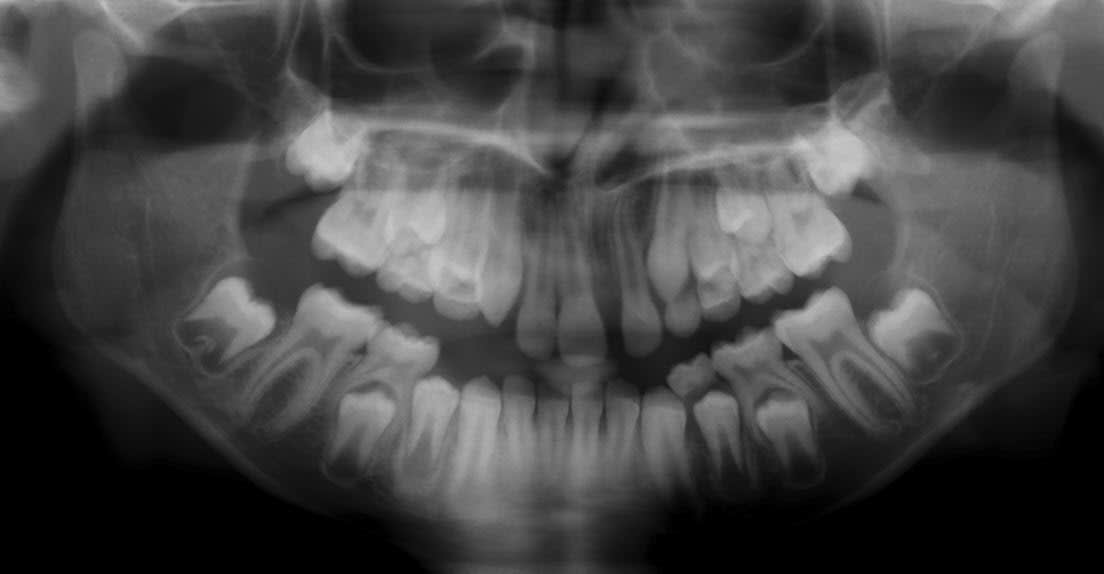

Voici les clichés radios demandés. Cette jeune fille a 7 ans.

Je crois que la décision orthodontique peut attendre car les racines des incisives n'ont pas fini leur formation. Il reste deux problèmes: le cote esthétique et la classe II!